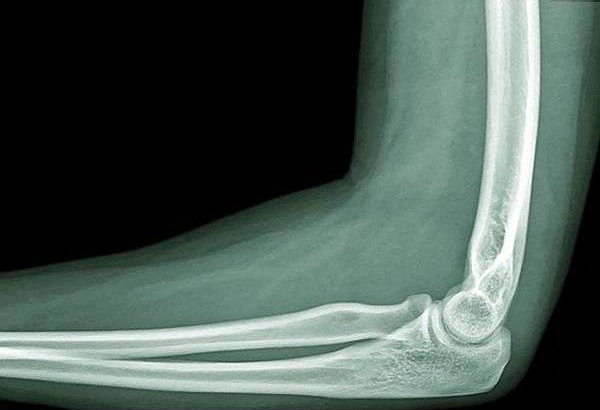

Запитання 19

РОЗПІЗНАЙТЕ КІСТКУ. ПЕРЕЛОМ ЯКОЇ ЇЇ ЧАСТИНИ ВИ БАЧИТЕ НА РЕНТГЕНОГРАМІ?

варіанти відповідей

ULNA

RADIUS

FEMUR, ШИЙКА

ПРОКСИМАЛЬНОГО ЕПІФІЗА

ДИСТАЛЬНОГО ЕПІФІЗА

ДІАФІЗА

ЛІКТЬОВОГО ВІДРОСТКА

ПРОМЕНЕВОГО ВІДРОСТКА